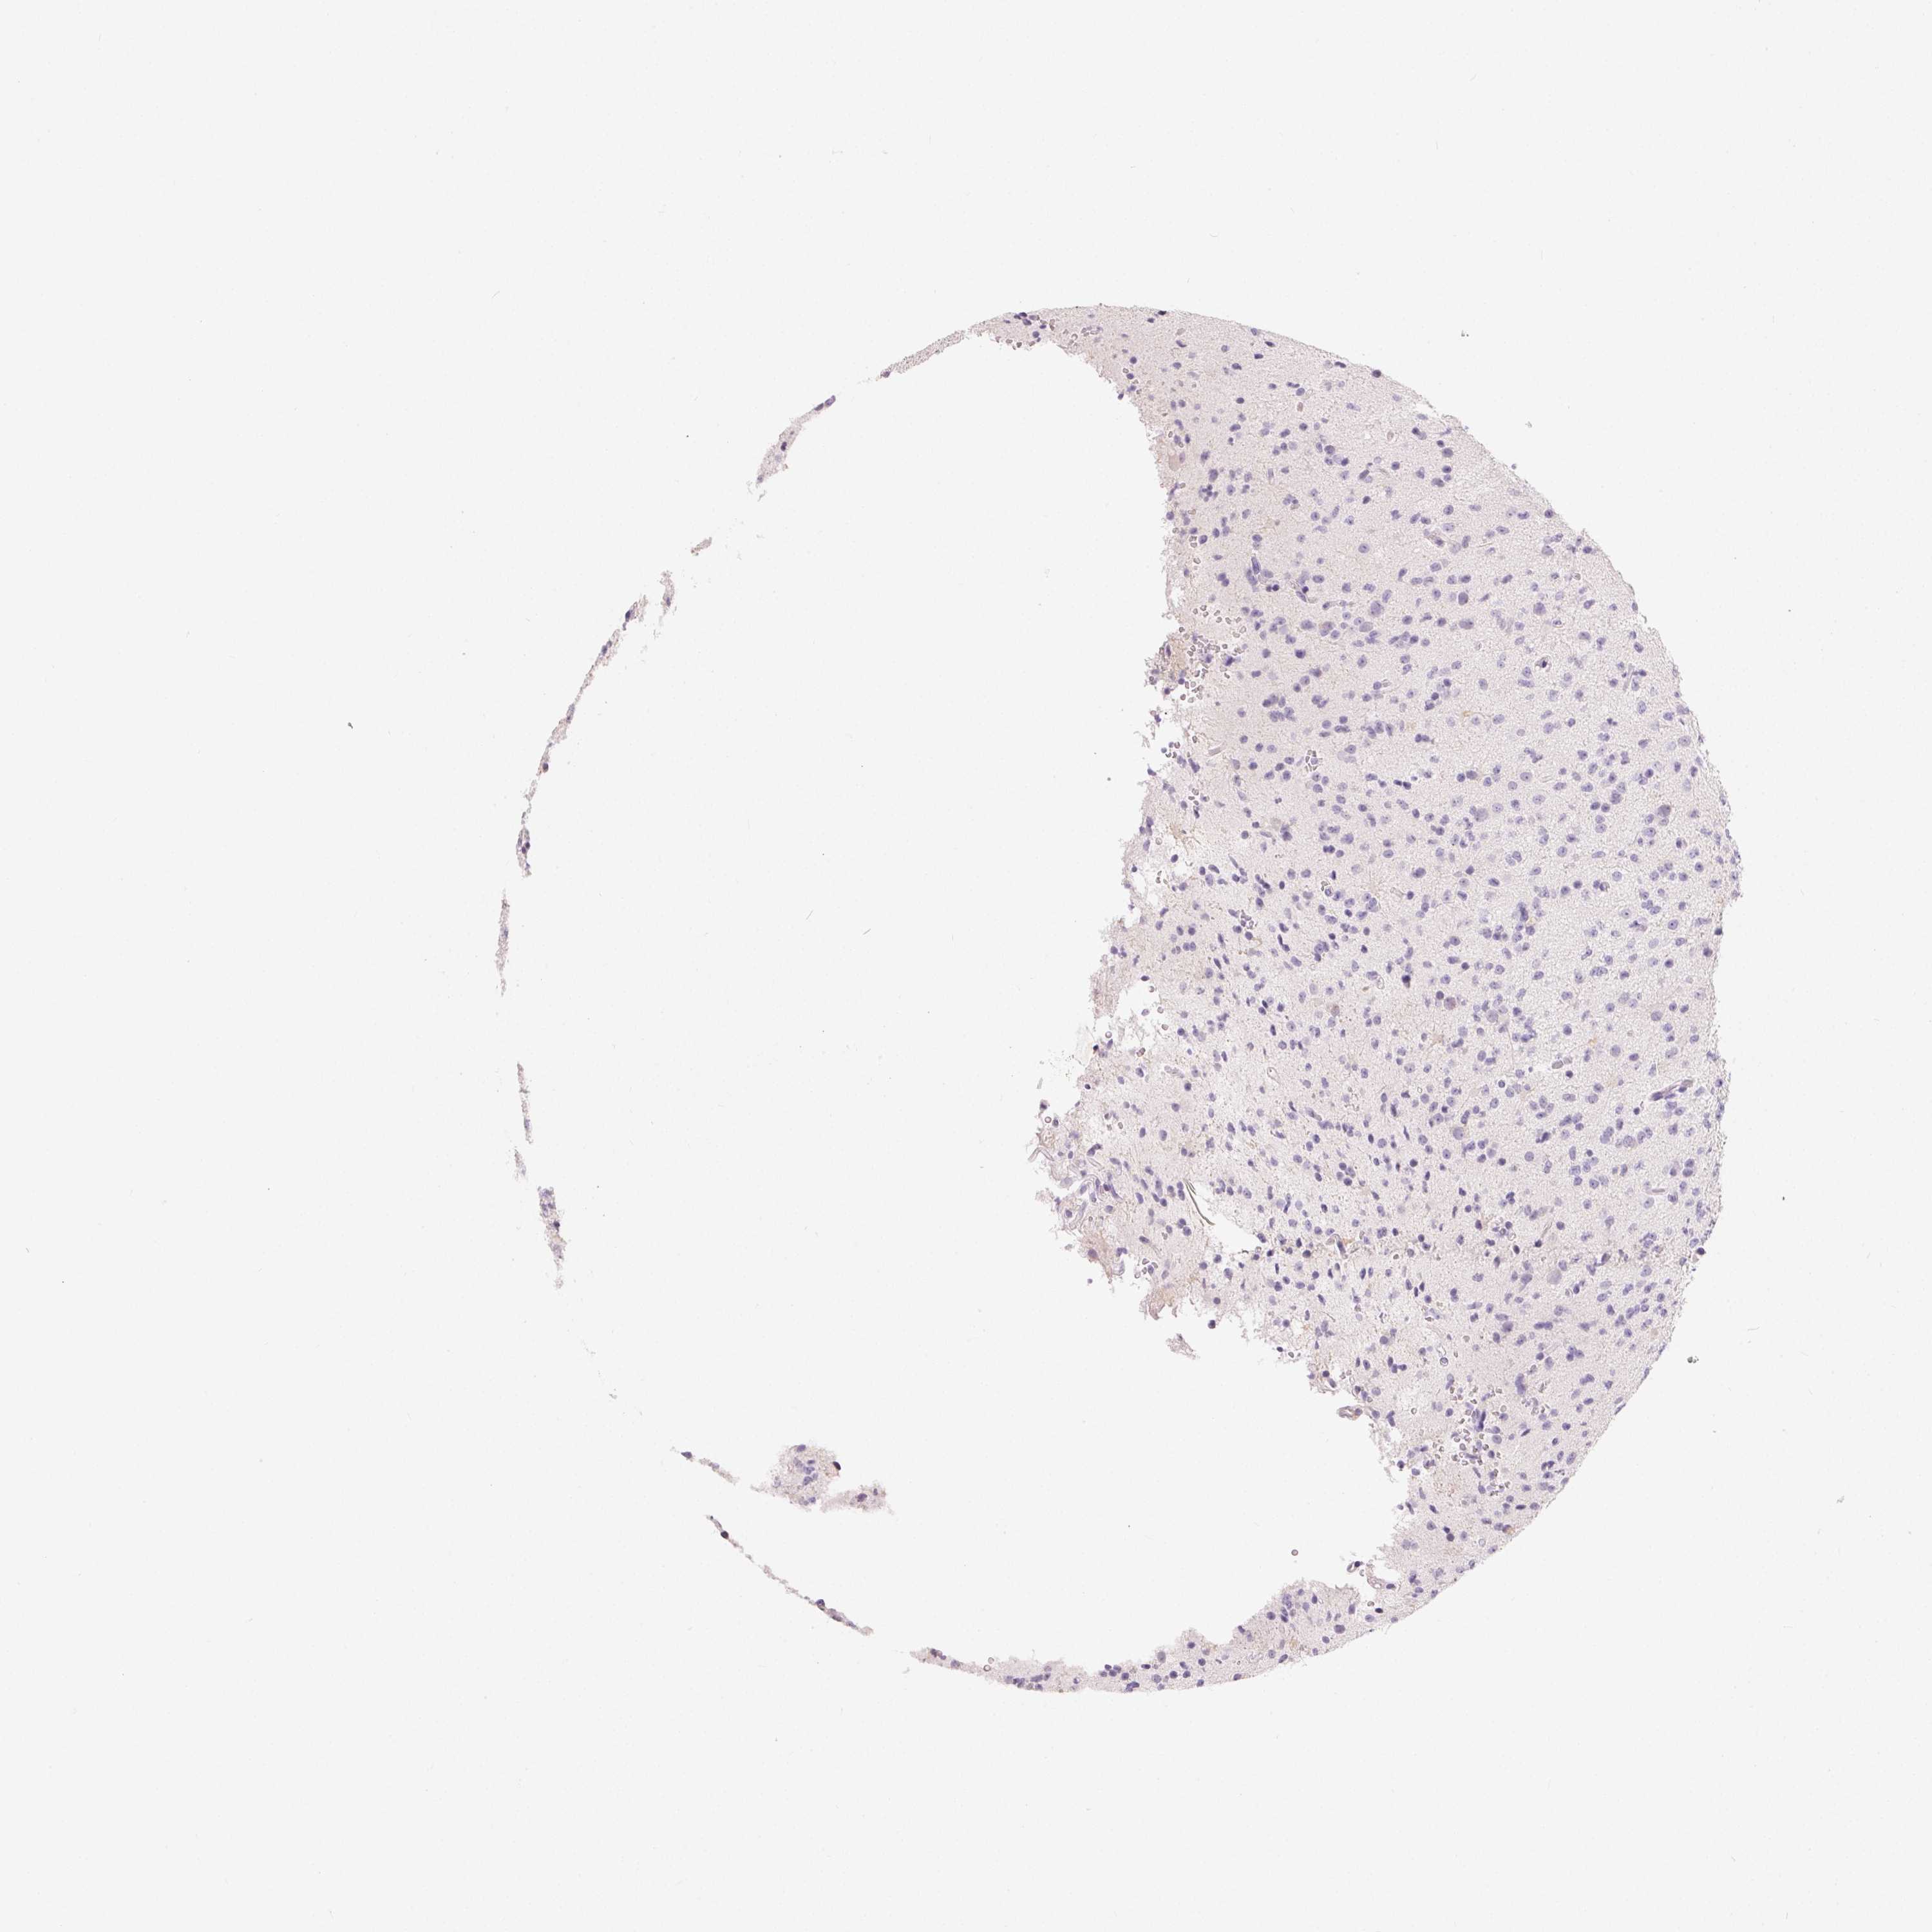

GLIOMA - Protein expressioni

A mouse-over function shows sample information and annotation data. Click on an image to view it in a full screen mode. Samples can be filtered based on level of antibody staining by selecting one or several of the following categories: high, medium, low and not detected. The assay and annotation is described here.

Note that samples used for immunohistochemistry by the Human Protein Atlas do not correspond to samples in the TCGA dataset.

Antibody stainingi

Antibody staining in the annotated cell types in the current human tissue is reported as not detected, low, medium, or high, based on conventional immunohistochemistry profiling in selected tissues. This score is based on the combination of the staining intensity and fraction of stained cells.

Each image is clickable and will lead to virtual microscopy that enables deeper exploration of all samples and also displays staining intensity scores, fraction scores and subcellular localization as well as patient and tissue information for each sample.

Antibody HPA039451

Antibody HPA039562

Staining

High

Medium

Low

Not detected

Intensity

Strong

Moderate

Weak

Negative

Quantity

>75%

75%-25%

<25%

None

Location

Nuclear

Cytoplasmic/membranous

Cytoplasmic/membranous,nuclear

Glioma, malignant, Low grade

Glioma, malignant, High grade

Glioblastoma, NOS